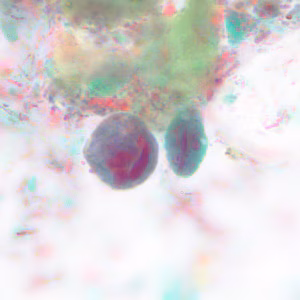

Case #228 – May, 2008

Within a week of returning from a conference in Mexico, a 28-year-old woman presented to her primary care physician with cramps, abdominal pain, gas and diarrhea. A routine Ova and Parasite (O&P) examination was performed on stool specimens. Figures A–F show objects observed on a trichrome-stained slide prepared from the stool. All images were taken at 1000x oil magnification. The objects in Figures A–C measured 12 micrometers. The objects in Figures D and E averaged 10 micrometers. The object in Figure F measured 12 micrometers in diameter. What is your diagnosis? Based on what criteria?

Figure B